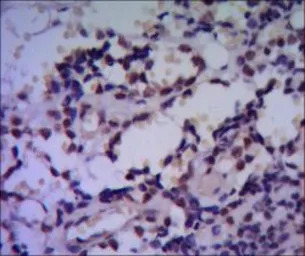

IHC-P analysis of human breast cancer using GTX82827 HSPA4 antibody [5A6].